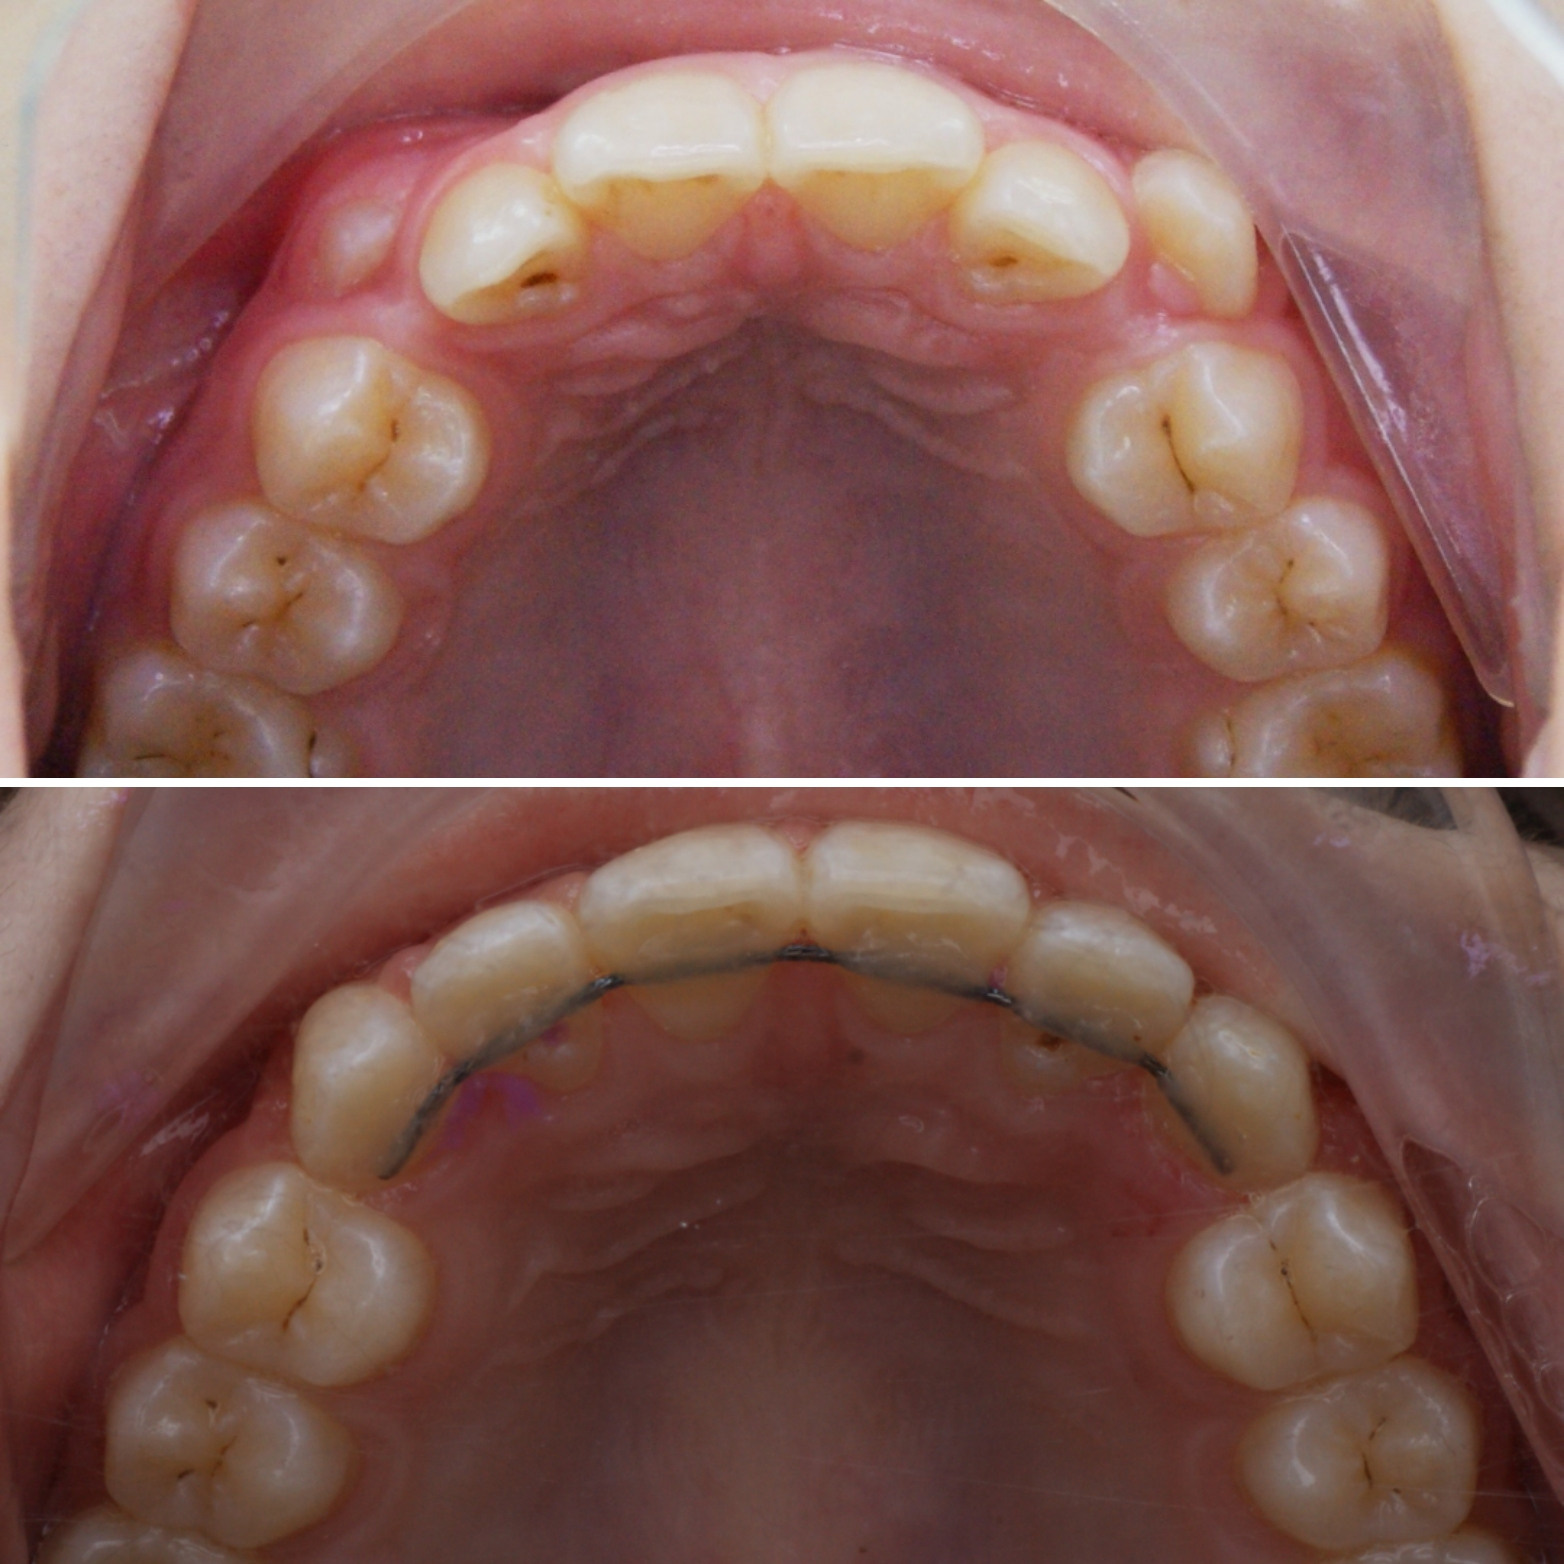

КОНСТРУКЦИЯ АППАРАТА МАРКО РОСА

1️⃣ ВИНТ ХАЙРЕКС. Создаёт расширяющее усилие.

2️⃣ МЕТАЛЛИЧЕСКИЕ ЛАПКИ. Это дополнительные элементы фиксации, которые упираются в молочные клыки, создают точки приложения силы к зубному ряду.

3️⃣ КОЛЬЦА НА МОЛОЧНЫЕ МОЛЯРЫ. Обеспечивают фиксацию аппарата на опорных зубах с помощью специального стоматологического клея.

4️⃣ ПЛАСТМАССОВЫЙ БАЗИС (пластинка). Объединяет все элементы в единую систему и передаёт расширяющее усилие винта на нёбо.

5️⃣ ДОПОЛНИТЕЛЬНЫЕ ЭЛЕМЕНТЫ (крючки для лицевой маски)

*️⃣ Спанч Боб и Патрик😀

Аппарат Марко Роса (Marco Rosa) - маленький невидимый помощник в больших ортодонтических делах💗